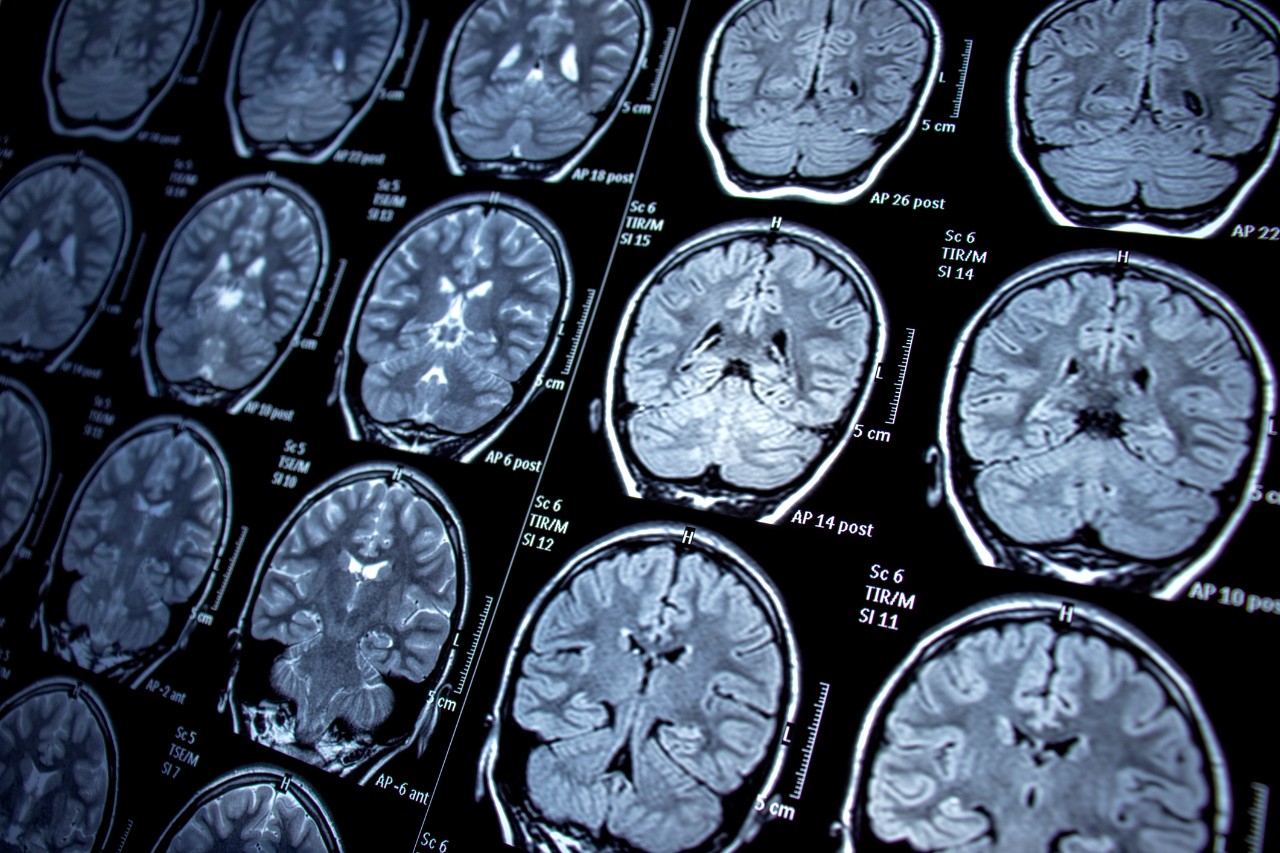

To interrupt that process, Dr. Norman’s team has developed a treatment. He hopes to soon test it in human trials. It would target and reduce concentrations of the drug at the site of action in the brain. That will hopefully lead to reduced use and long-term addiction recovery. This also likely has implications for other drugs.

Lead photo/Nur Ceren Demir/iStock